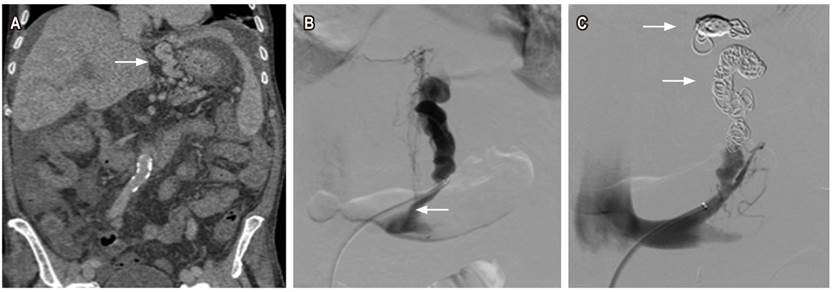

Primer caso

Paciente masculino de 74 años con antecedente de hepatocarcinoma metastásico y cirrosis, con invasión tumoral de la vena porta, quien consulta por un cuadro de dos días de deposiciones melénicas. Se realiza una endoscopia de vías digestivas altas (EVDA) en la que se encuentran várices esofágicas pequeñas sin estigmas de sangrado, una várice de aproximadamente 15 mm con signos rojos a nivel subcardial hacia el fondo gástrico y una zona ulcerada en la superficie sin sangrado activo. Se considera que el paciente tiene sangrado digestivo alto portal hipertensivo secundario a una várice fúndica grande, y no es candidato a manejo endoscópico, por lo cual se solicita una valoración por radiología intervencionista; allí le toman una tomografía de abdomen en la que se hayan várices tortuosas adyacentes a la curvatura menor del estómago (Figura 1A). Se realiza una venografía selectiva opacificando las várices tortuosas en una curvatura menor, con algunas venas de drenaje paraespinales, un shunt gastrorrenal (Figura 1B) y una embolización con coils (Figura 1C) ocluyendo el flujo en várices. El procedimiento se realizó sin complicaciones, por lo que se dio egreso a los dos días.